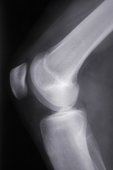

X-ray of a knee.Acupuncture is usually not sufficient treatment for a broken bone. In most cases, the bone needs to be set by a qualified orthopedic surgeon. A cast, splint, or sometimes surgery is often needed. There is a delicate balance between resting a broken bone long enough for the bone to heal and resting it so long that the surrounding soft tissue loses too much muscle tone which leads to longer healing and rehabilitation.

Once you have seen the orthopedic specialist and have your cast, come to the acupuncturist! Acupuncture can improve the blood flow, reduce the pain during the healing process, help to maintain muscle tone without exercising, and generally improve the quality of your recovery. back to top